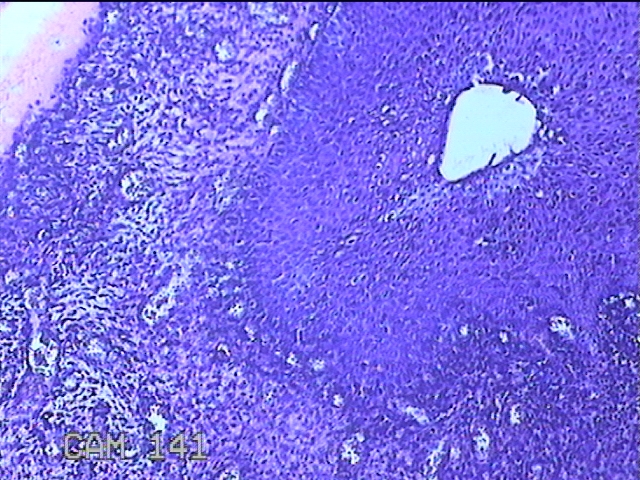

宫颈赘生物

性别

女

年龄

49岁

临床诊断

人乳头瘤病毒感染

一般病史

宫颈HPV阳性TCTLSLL

标本名称

大体所见

灰白粉红色肿物1.2x0.8x0.2cm两个,表面光滑。